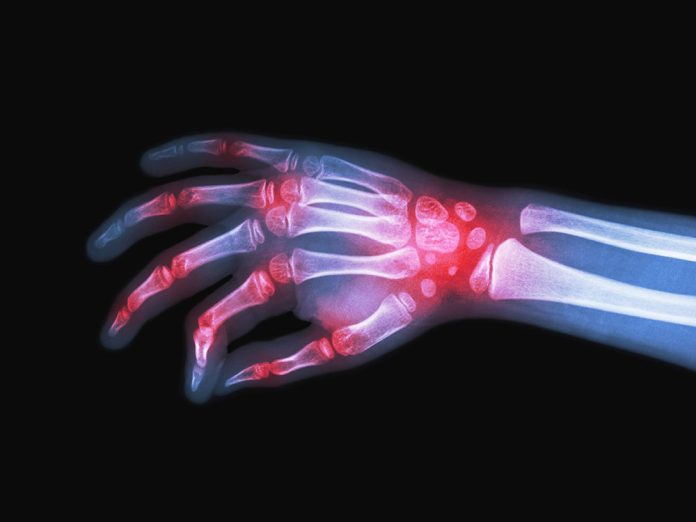

As doenças reumáticas acometem o aparelho locomotor, ou seja, ossos, articulações, cartilagens, músculos, tendões e ligamentos. Algumas também podem comprometer outras partes do corpo humano como rins, coração, pulmão, pele, sistema circulatório, cérebro e o sistema nervoso central. Essas enfermidades reumáticas estão entre as principais causas de afastamentos do trabalho e podem levar a limitações físicas se não diagnosticadas e tratadas adequadamente. Entre os sintomas mais frequentes estão dores nas articulações, rigidez e inchaço, que podem, dependendo do estágio da doença, levar à deformidade nos pés e nas mãos, desgaste nas cartilagens e nos ossos.

A osteoartrite ou artrose, de acordo com a SBR, é a doença reumática mais frequente no país, representando cerca de 30% a 40% das consultas em ambulatórios de reumatologia. Já a artrite reumatoide, doença de natureza inflamatória, crônica e progressiva, acomete cerca de dois milhões de pessoas no Brasil. Trata-se de uma doença mais prevalente entre mulheres, na faixa dos 30 aos 55 anos, mas também atinge pessoas de todas as idades, inclusive crianças e adolescentes.

Com a preocupação de alertar e conscientizar a população, especialistas da Sociedade Brasileira de Reumatologia (SBR) estarão em contato direto com a população esclarecendo dúvidas em relação a doenças reumáticas como Artrite Reumatoide, Fibromialgia, Osteoporose, Osteoartrite/Artrose, Espondiloartrites, Artrite Psoriásica, Lombalgia, Lúpus Eritematoso Sistêmico (LES), Gota, Febre Reumática, Vasculites, Doença de Sjögren, Doença de Behçet, Esclerose Sistêmica (ES) e outras. Cada doença tem sua característica. A artrite reumatoide, por exemplo, é uma doença crônica e ocorre quando há uma alteração do sistema imunológico, que ataca as articulações.

De acordo com o especialista, o diagnóstico e o tratamento nas fases iniciais das doenças reumatológicas são muito importantes para que o paciente consiga ter uma vida produtiva e de qualidade. “Dores nas articulações podem ser sintomas de doenças reumáticas, como artrite e osteoartrite/artrose, e devem ser investigadas, diagnosticadas e tratadas de forma adequada por um reumatologista”, ressalta.